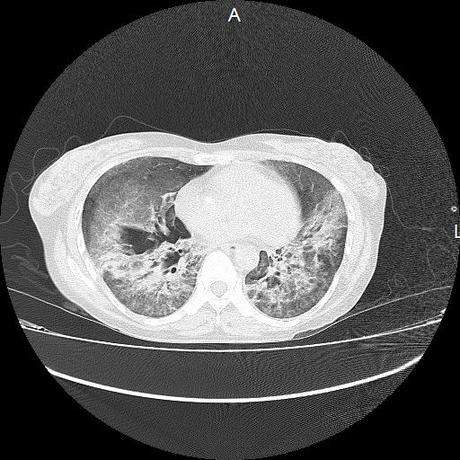

El parénquima pulmonar con areas parcheadas difusas en vidrio despulido combinadas con otras areas hipodensas de baja atenuación debidas a atrapamiento aéreo y engrosamiento intersticial y zonas de fibrosis de predominio en lóbulos medios e inferiores de ambos pulmones.

- LOS HALLAZGOS PUEDEN ESTAR EN RELACIÓN A NEUMOPATIA INTERSTICIAL PROBABLE ETIOLOGIA HIPERSENSITIVA VS AUTOINMUNE/BACTERIANA/FUNGICA.